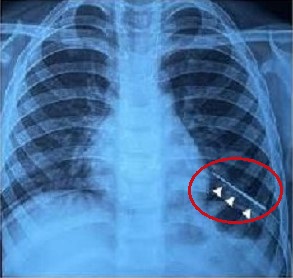

बाल चिकित्सा सर्जरी विभाग के अतिरिक्त प्रोफेसर डॉ. विशेष जैन ने खुलासा किया कि बच्चे को खांसी में खून आने के कारण पिछले बुधवार को गंभीर हालत में एम्स में भर्ती कराया गया था। रेडियोलॉजिकल जांच से पता चला कि बच्चे के बाएं फेफड़े में एक लंबी सिलाई सुई गहराई तक धंसी हुई है। इस नाजुक प्रक्रिया से निपटने के लिए, डॉक्टरों ने 4 मिमी चौड़ाई और 1.5 मिमी मोटाई का एक चुंबक खरीदा जिसकी मदद से सूई निकाली गई।

उनके आविष्कार में एक विशेष रूप से तैयार किया गया उपकरण शामिल था, जो चुंबक को रबर बैंड और धागों से सुरक्षित रूप से चिपका देता था। बाएं फेफड़े के अंदर सुई का पता लगाने के लिए श्वासनली की एक एंडोस्कोपी शुरू की गई, जिसमें केवल सुई की नोक का पता चला जो गहराई में धंसी हुई थी। चुंबकीय उपकरण सुई को सफलतापूर्वक निकालने में सहायक साबित हुआ।